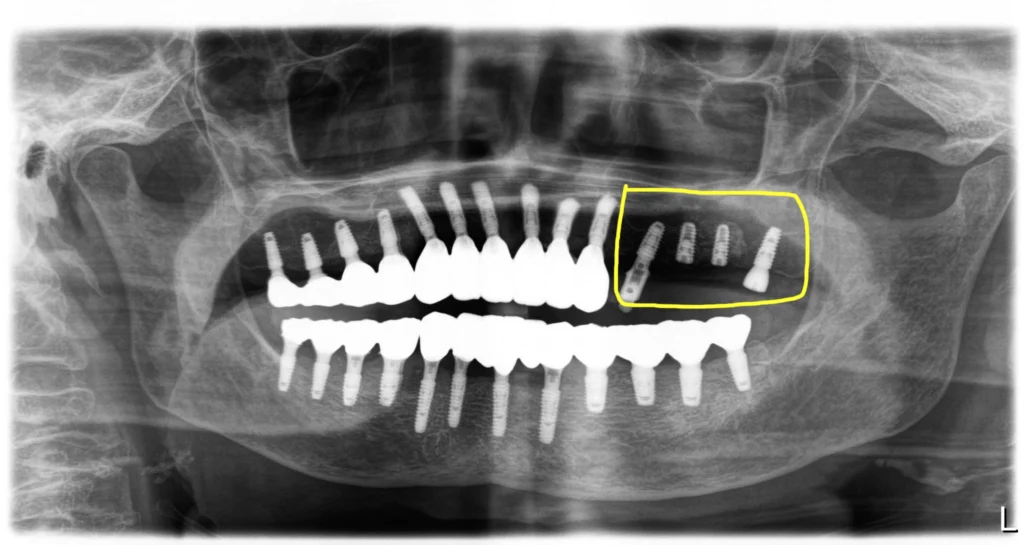

1차 수술시에 식립한 대부분의 임플란트를 먼저 최종보철을 만들어 끼운 상태입니다. 추가식립 부위는 3개월 이후에 다시 마무리를 하더라도 식사를 편하게 해 드리려고 먼저 치료를 해 드렸어요.

노랑색 네모 부분은 3개월 뒤에 다시 스캔을 해서 최종보철을 마무리해야 합니다.